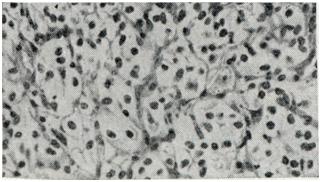

Рис. 1.

Ангиоретикулема. Полигональные светлые клетки в петлях сосудистой сети. Видна хроматиновая зернистость (окраска гематоксилинэозином; ×200).

Микроскопически в ткани ангиоретикулемы обнаруживаются два компонента: 1) густая сеть сосудов капиллярного типа, имеющих вид каналов, щелей, более широких крововместилищ; стенки сосудов образованы одним слоем клеток эндотелия, 2) полигональные клетки со светлой цитоплазмой и небольшим ядром, содержащим нежную хроматиновую зернистость, располагающиеся между сосудами (рис. 1). Местами границы между клетками не видны или клетки формируют ретикулярную структуру. Часто цитоплазма содержит включения анизотропных липоидов («пенистые», «ксантомные» клетки).